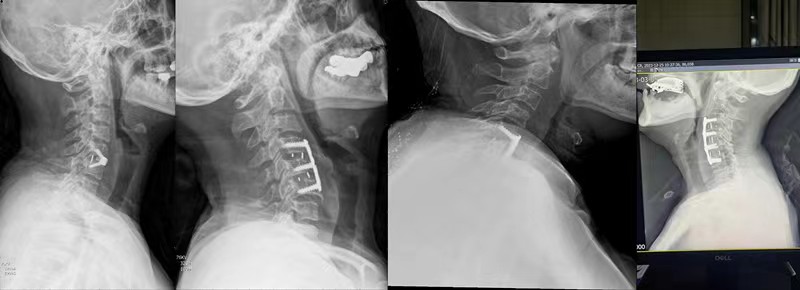

该患者为54岁维吾尔族男性,患者入院时行走已经较为困难,需家人搀扶,四肢无力、僵硬伴左上肢剧烈疼痛3月,因为手术风险极大,慕名新疆维吾尔自治区人民医院驻疆骨科专家前来就诊。杨宝辉医生接诊时发现该患者约80%的脊髓被突出的椎间盘及部分钙化物压扁,手术难度高,风险系数大,术中极有可能出现四肢瘫痪,缺血再灌注损伤等,这些无疑表明这是一个风险极高,难度极大的手术。但手术是患者唯一的选择,是挽救患者神经功能的唯一希望,在困难面前杨宝辉副主任医师决定迎难而上。

为了最大程度减少术中创伤,最终选择了颈前路单间隙减压植骨融合内固定的手术方式,并于2024年1月7日如期进行。术中杨医生发现椎体后缘几乎没有间隙,他机智地选择超声刮勺及神经勾巧妙配合,刮除钙化组织并缓慢勾出脱出的椎间盘组织,彻底显露硬膜及双侧钩椎关节,实现了彻底减压并置入融合器,最终神经诱发电位显示波幅上升,标志着手术的圆满成功。

近1月来杨宝辉副主任医师已经完成近10例难度较高的颈椎病手术,其中有单节段,有双节段,甚至三节段,既有单纯椎间盘突出,又有后纵韧带骨化症等,手术方式既有ACDF、ACCF等,他以其精湛的艺术赢得了患者的肯定和区医院医生们的尊敬,为区中建设起到了良好的助推作用。